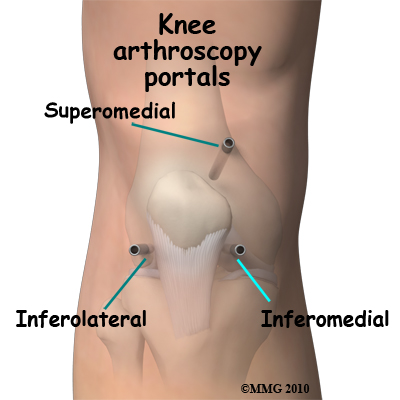

The surgeon begins the operation by making two or three small openings into the knee, called portals. These portals are where the arthroscope and surgical instruments are placed inside the knee. Care is taken to protect the nearby nerves and blood vessels. A small metal or plastic tube (or cannula) will be placed through one of the portals to inflate the knee with sterile saline, which allows the tissues inside the joint to be more easily visible.

The surgeon begins the operation by making two or three small openings into the knee, called portals. These portals are where the arthroscope and surgical instruments are placed inside the knee. Care is taken to protect the nearby nerves and blood vessels. A small metal or plastic tube (or cannula) will be placed through one of the portals to inflate the knee with sterile saline, which allows the tissues inside the joint to be more easily visible.

The surgeon begins the operation by making two or three small openings into the knee, called portals. These portals are where the arthroscope and surgical instruments are placed inside the knee. Care is taken to protect the nearby nerves and blood vessels. A small metal or plastic tube (or cannula) will be placed through one of the portals to inflate the knee with sterile saline, which allows the tissues inside the joint to be more easily visible.